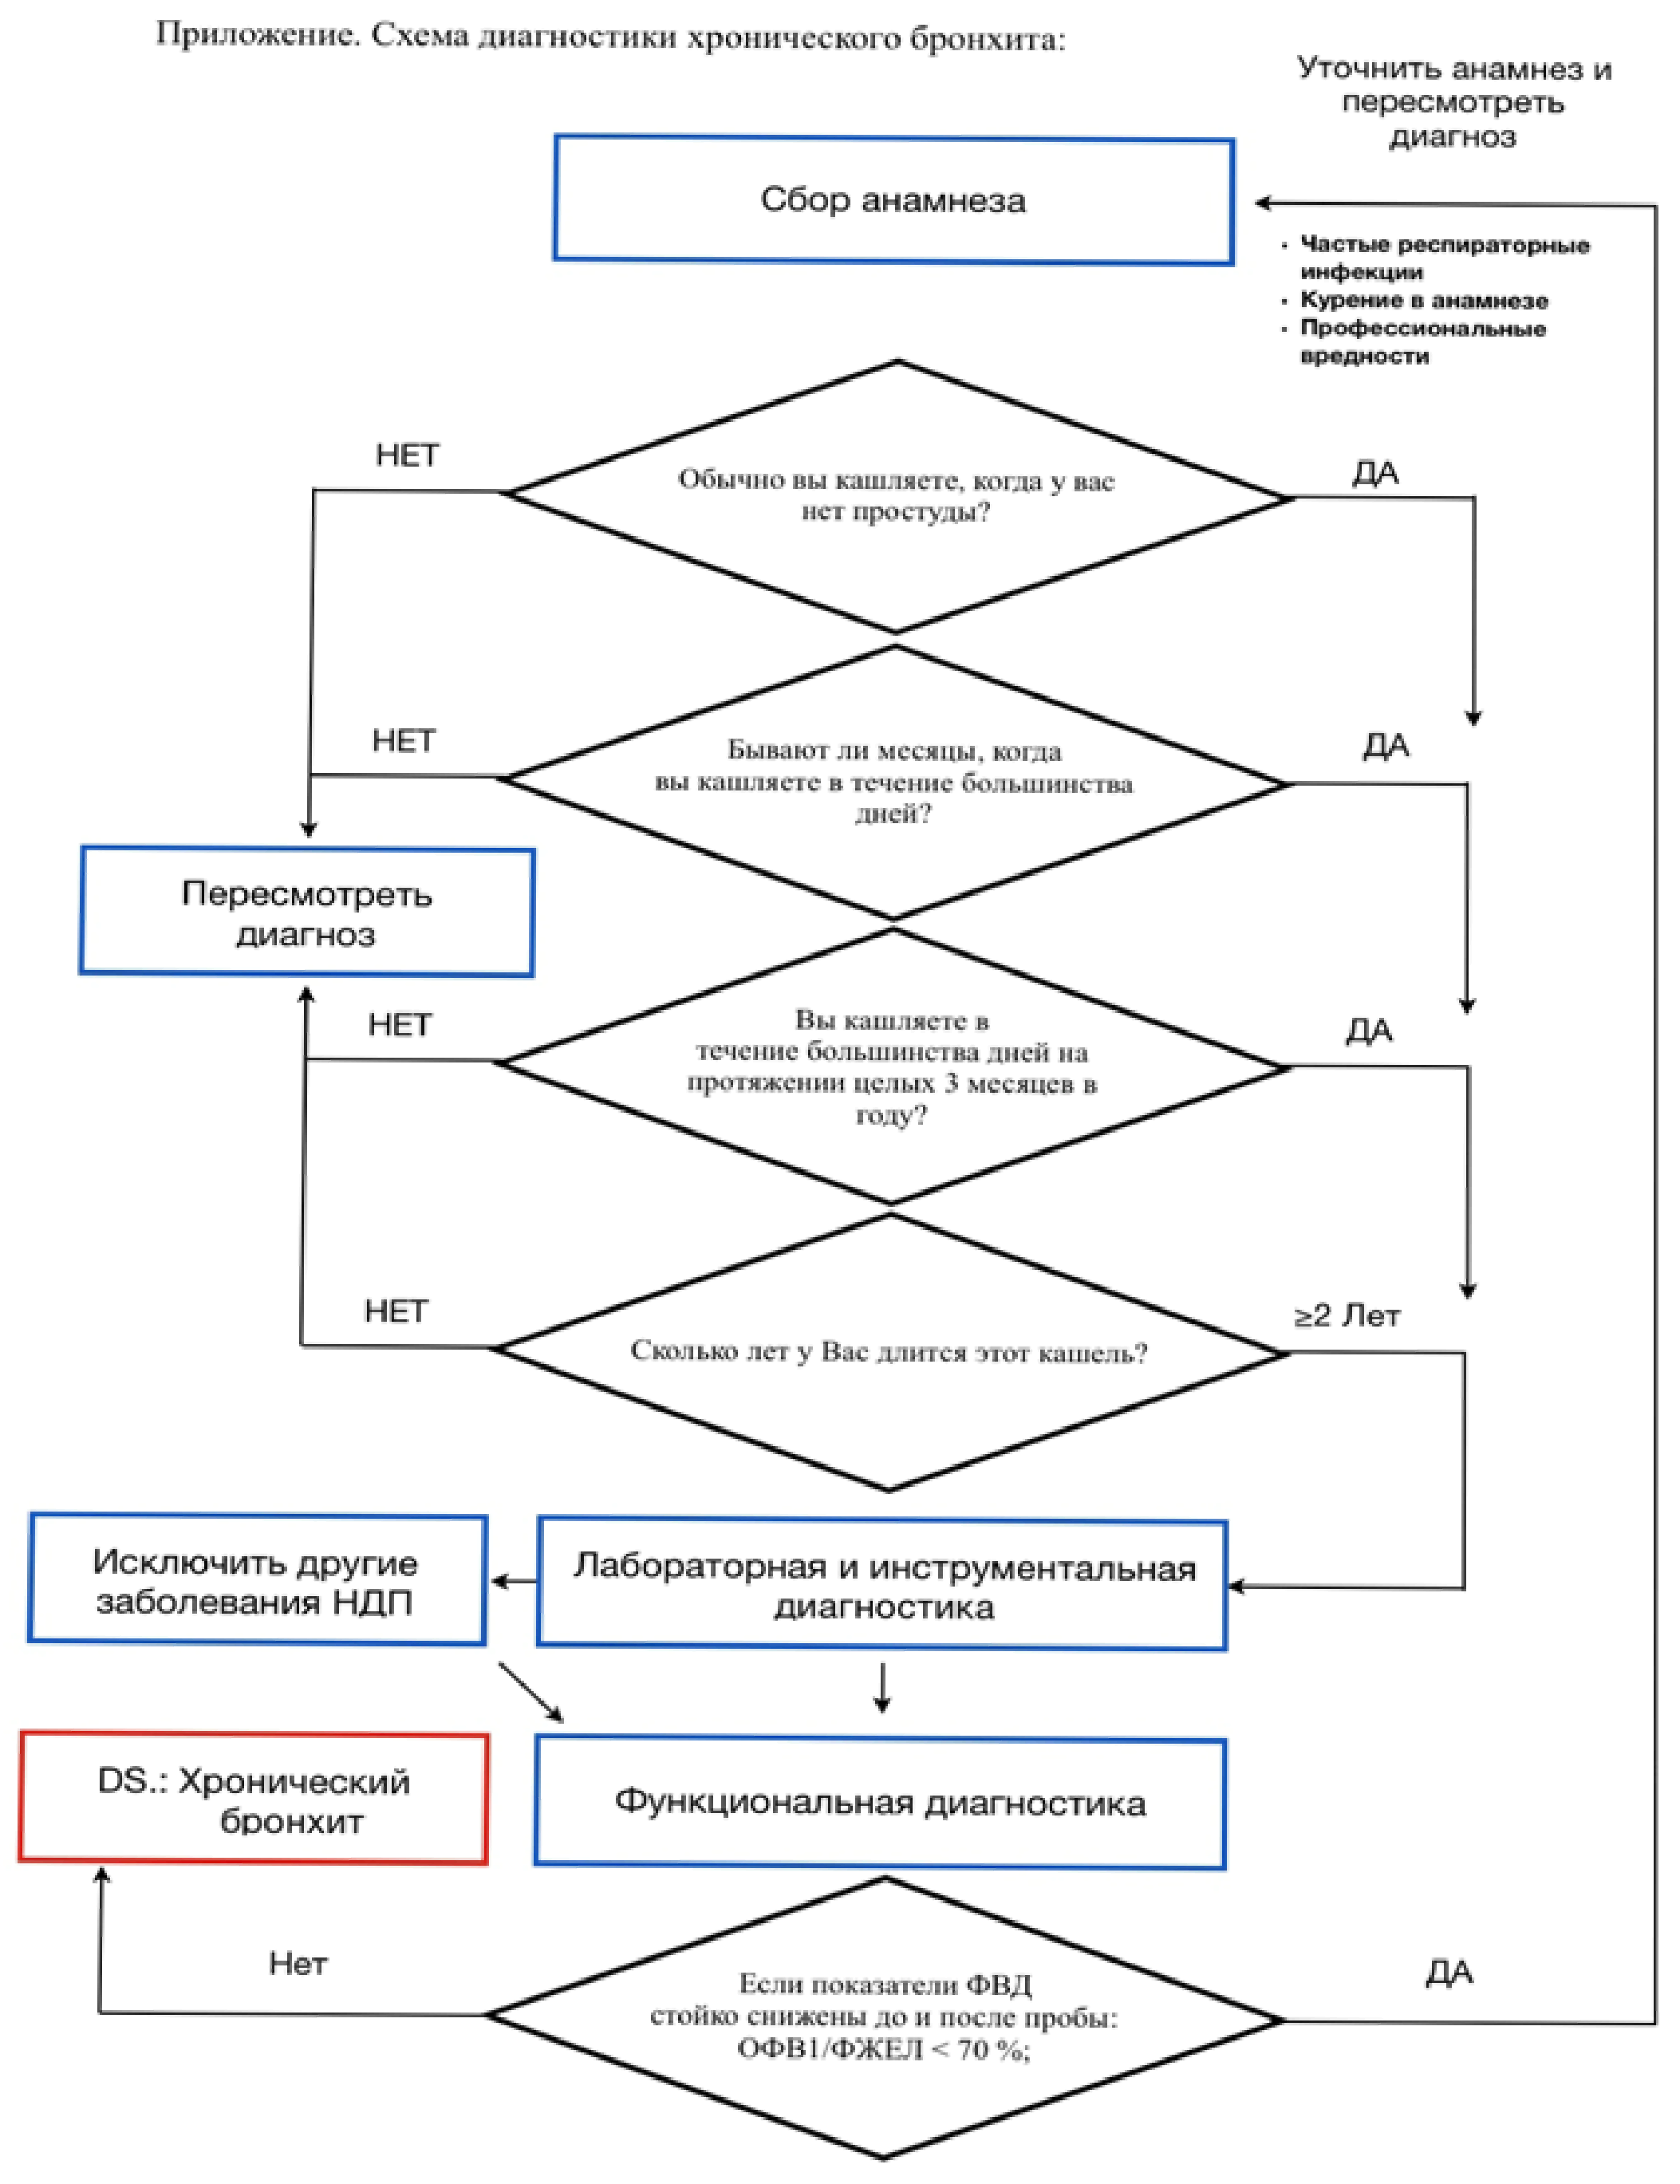

Гипердиагностика ХБ среди пациентов и врачей весьма распространена. В Соединенных Штатах, по оценкам национальных опросов, проведенных Национальным центром статистики здравоохранения, показано, что 16 миллионов человек страдают ХОБЛ. Из них, около 14 миллионов страдали ХБ, а 2 миллиона эмфиземой легких. Предполагается, что эти статистические данные занижают распространенность ХОБЛ на целых 50%, поскольку многие пациенты не критично относятся к своим симптомам, и заболевание остается не диагностированным. Подавляющее большинство людей (88,4%), которые сообщили о диагнозе ХБ, о котором сообщили сами или диагноз был подтвержден врачом, не соответствовали стандартным критериям ХБ.

Критерии установления диагноза:

- "Кашлевой анамнез" (кашель малопродуктивный или с выделением мокроты в течение 3 месяцев не менее 2-х лет)

- Отсутствие другой патологии бронхолегочного аппарата (туберкулез, бронхоэктатическая болезнь, пневмония, бронхиальная астма, рак легкого и др.), обусловливающей "кашлевой анамнез"

- Выявление обструкции дыхательных путей (ее обратимого и необратимого компонента) при дифференциальной диагностике ХОБЛ.

Дифференциальная диагностика хронического бронхита проводится с заболеваниями, сопровождающимися синдромом хронического кашля (кашель, продолжающийся более 8 нед.) [22-24].

Учитывая родственность факторов риска, близость патоморфологических изменений на уровне крупных дыхательных путей, и, как следствие этого, схожесть клинических проявлений (хронический продуктивный кашель), чаще всего перед практикующим врачом возникает необходимость в разграничении ХБ и ХОБЛ.

Наиболее простым и демонстративным в этом случае является исследование неспровоцированных дыхательных объемов и потоков с бронхолитической пробой. Формализованным спирометрическим критерием ХОБЛ является ограничение воздушного потока ( [1] < 0,7), тогда как у пациентов с ХБ вне обострения исследуемые параметры функции внешнего дыхания оказываются близкими к должным [21].

[1] < 0,7), тогда как у пациентов с ХБ вне обострения исследуемые параметры функции внешнего дыхания оказываются близкими к должным [21].

Исследование функции внешнего дыхания

- Рекомендуется исследование неспровоцированных дыхательных объемов и потоков с целью выявления рестриктивных и обструктивных нарушений лёгочной вентиляции у пациентов с ХБ при дифференциальной диагностике с ХОБЛ для определения ФВД:  , ЖЕЛ, ФЖЕЛ,

, ЖЕЛ, ФЖЕЛ,  [24].

[24].

Уровень убедительности рекомендаций С (уровень достоверности доказательств - 5)

Комментарии: При стабильном течении ХБ показатели ФВД в пределах нормальных значений.

Стабильное течение ХБ (фаза клинической ремиссии) с функциональной точки зрения сопровождается постбронходилататорным отношением  , при этом, бронходилатационный тест с сальбутамолом** 400 мкг отрицательный (прирост

, при этом, бронходилатационный тест с сальбутамолом** 400 мкг отрицательный (прирост  менее 12% и менее 200 мл от исходной величины). ХБ с обструктивным синдромом может сопровождаться нарушениями ФВД что требует, с учетом клинико-анамнестических и лабораторных данных дифференциальной диагностики с ХОБЛ (при постбронходилататорной величине ОФВ1/ФЖЕЛ < 0,7) или с БА (при положительном бронходилатационном ответе (приложение Г3) [9, 21].

менее 12% и менее 200 мл от исходной величины). ХБ с обструктивным синдромом может сопровождаться нарушениями ФВД что требует, с учетом клинико-анамнестических и лабораторных данных дифференциальной диагностики с ХОБЛ (при постбронходилататорной величине ОФВ1/ФЖЕЛ < 0,7) или с БА (при положительном бронходилатационном ответе (приложение Г3) [9, 21].